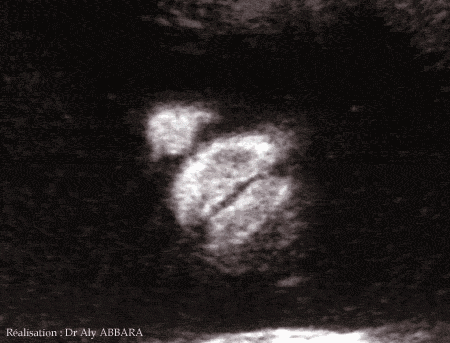

Bouche fœtale ouverte et fermée à 29 semaines d'aménorrhée